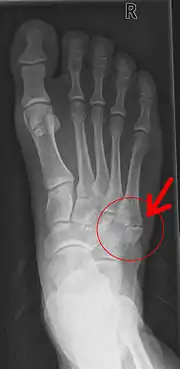

Pseudarthrose de la base du 5e métatarsien après un arrachement osseux.

On parle plus précisément de pseudarthrose en cas de persistance du trait de fracture plus de 6 mois après la lésion initiale.